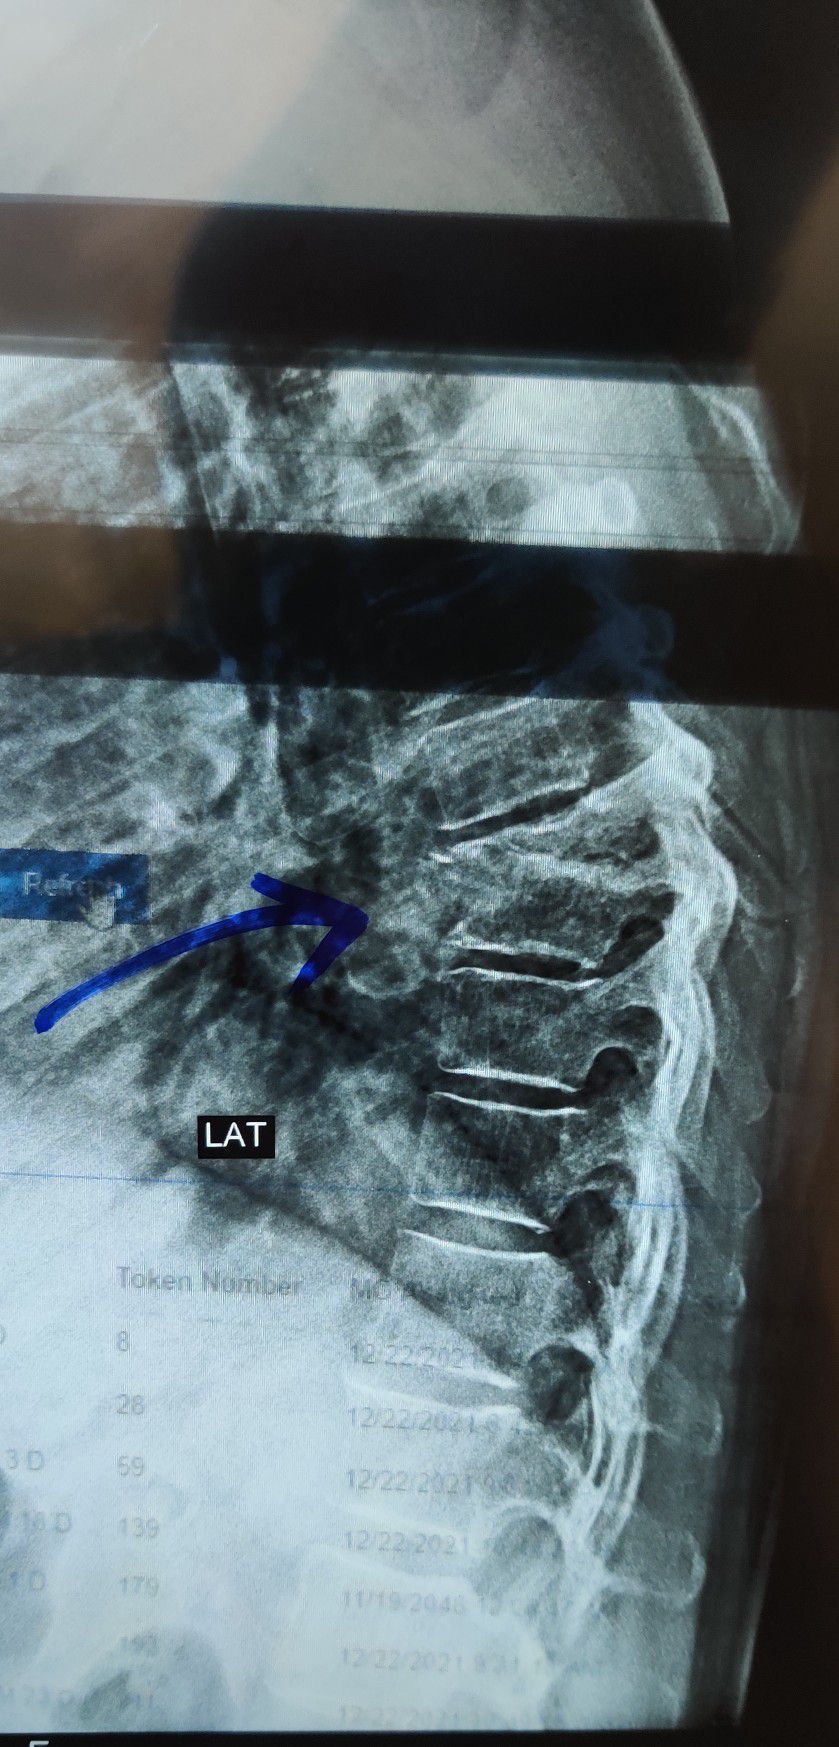

Potts Disease. Can you describe the findings in this Thoracolumbar X Ray of spine?

Xray

Spine

Thoracolumbar